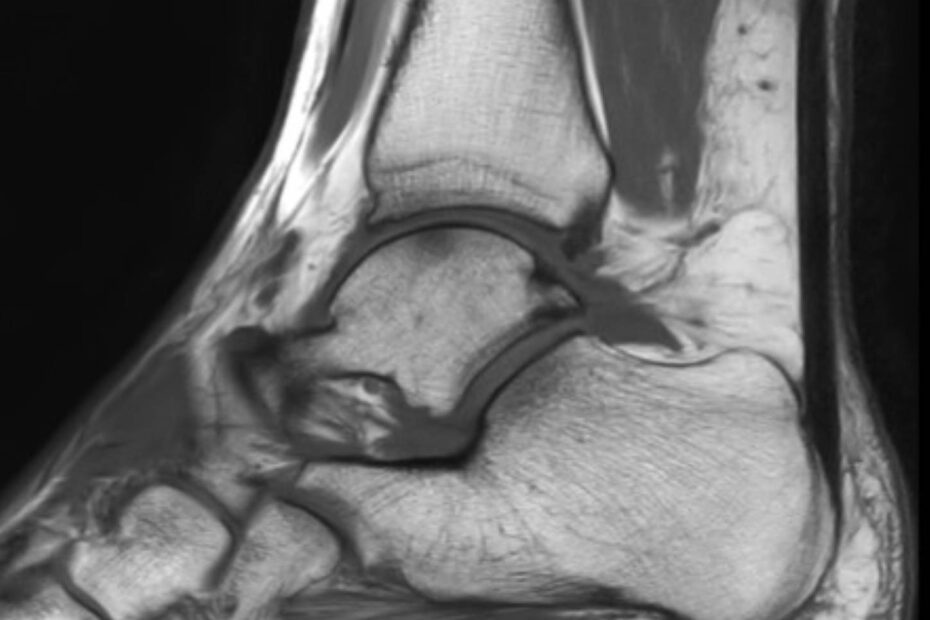

Eine Magnetresonanztomographie des Sprunggelenks, auch MRT Sprunggelenk oder MRT OSG genannt, ist ein bildgebendes Verfahren, das es ermöglicht, das Sprunggelenk mit allen Strukturen präzise und detailliert darzustellen. Die Ursache für Schmerzen oder Schwellungen im Sprunggelenk können durch eine MRT lokalisiert werden. Eine der häufigsten Verletzungen am Sprunggelenk ist das Supinationstrauma. Hierbei handelt es sich um … MRT Sprunggelenk weiterlesen